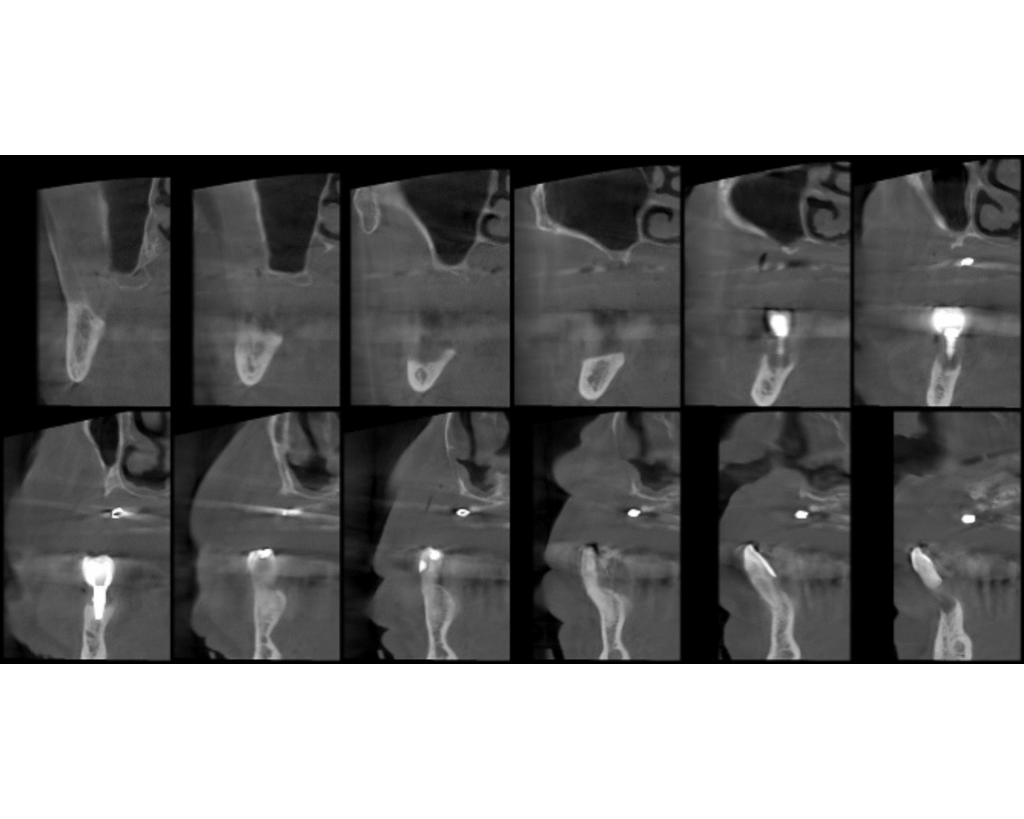

Radiográficamente se observa una atrofia severa de todo el maxilar superior, con pérdida del hueso total a nivel del seno maxilar derecho, probablemente por el fracaso de las intervenciones en el pasado, y áreas de apenas 1 mm de hueso en la zona antero superior. En el segundo cuadrante se observan restos de material, probablemente xenoinjerto, de los intentos de elevación sinusal en este lado. En la arcada inferior, se observa pérdida ósea generalizada, y acentuada a nivel del implante correspondiente al diente 46.